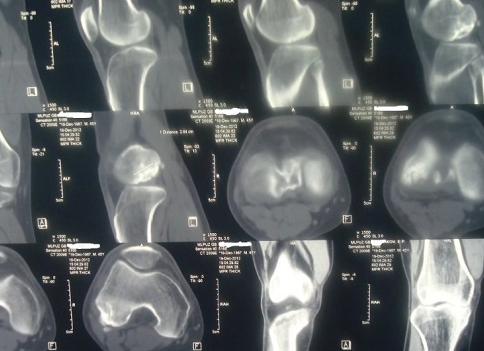

Мрт локтевого сустава

МРТ локтевого сустава: что показывает и как делают?

Этот диагностический метод имеет массу преимуществ, поэтому широко применяется во всех сферах медицины. Сущность МРТ заключается в воздействии магнитным полем на локтевой сустав и получении резонанса в виде радиосигналов.

МРТ локтевого сустава дает возможность получить точный результат исследования таких структур дистальной части плеча и проксимальной части предплечья: